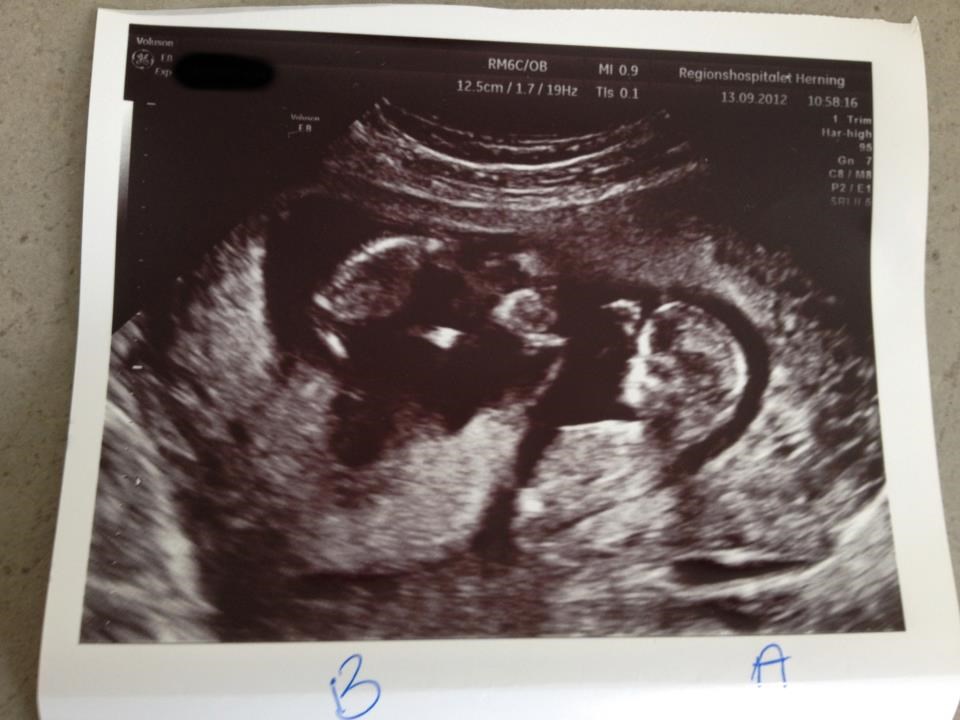

Dit nr 2 billed ligner meget mit fra 7+ og det var min blære der var nr 2 sorte bobel... Det er fordi den er forholdsvis fyldt... Hvis den var tom ville man næsten ikke kunne se den :-) jeg kunne dog ik mærke jeg skulle tisse før end hun scannede mig og trykkede på blæren

Man kan også se at den sorte bobel der er blæren er der ikke et foster i